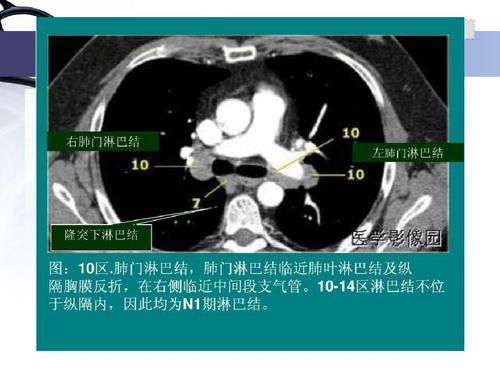

今日分享 — 纵隔淋巴结分区图谱

纵隔淋巴结分区图谱

纵隔淋巴结ct分区图谱